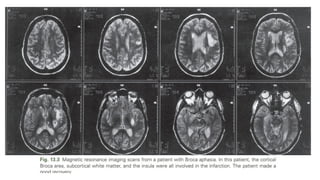

Features of Broca Aphasia

The lesions 

Broca area in the posterior part of the inferior frontal gyrus, along with damage

to adjacent cortex and subcortical white matter.

• Most patients with lasting Broca aphasia, including Broca original cases, have

much larger left frontoparietal lesions, including most of the territory of the

upper division of the left middle cerebral artery.

• Such patients typically evolve from global to Broca aphasia over weeks to

months.

• Patients who manifest Broca aphasia immediately after their strokes, by

contrast, have smaller lesions of the inferior frontal region, and their deficits

generally resolve quickly.

• lesions restricted to the lower precentral gyrus produced only

dysarthria and mild expressive disturbance.(In computed tomography (CT) scan

analyses at the Boston Veterans Administration Medical Center)

• Lesions involving the traditional Broca area (Brodmann areas 44 and

45) resulted in difficulty initiating speech

• lesions combining Broca area, the lower precentral gyrus, and

subcortical white matter yielded the full syndrome of Broca aphasia

(Alexander et al., 1990).